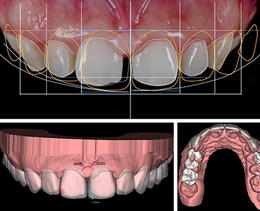

• tru-root牙根还原专利

牙冠与牙根的移动更整体有效

牙根到位效果更稳定

• tru-finish微笑美学设计

排齐牙齿、调整咬合

微笑设计,精确定制精准把控

精确数字化正畸摆脱了传统矫正精确度低等缺点,避免因托槽位置不精准而造成牙齿的往复运动,矫牙效果精确可控。在设计矫牙方案时,不仅还原咬合关系,更综合了现代颜面美学,实现矫牙的同时,重塑美丽笑线和脸型,矫牙变美快人一步。